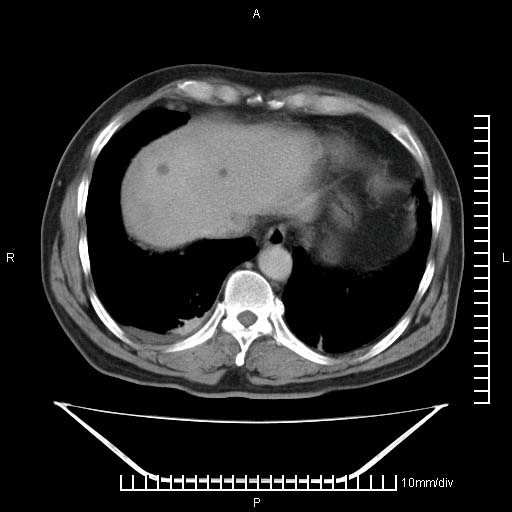

标题: CT25082:肝脏增强:男性,70岁 [打印本页]

标题: CT25082:肝脏增强:男性,70岁

患者以心脏疾病收住院,腹部无明显症状,b超查肝脏有占位。

增强效果不理想。考虑转移,胆囊壁明显增厚,不排除胆囊癌肝转移。

牛眼征,中心坏死无强化,外缘强化,最外缘又见低密度,考虑转移,与脓肿鉴别

肝内多发转移瘤,右下肺炎症并少量胸水。胃壁增厚建议胃镜,胰尾部“病变”为肠管。

1)肝脏多发性转移瘤(不排除胰尾癌转移所致可能)。2)腹水。3)右侧少量胸腔积液。

ct25082 结果:转移瘤

外院mr结果:胰尾恶性占位。